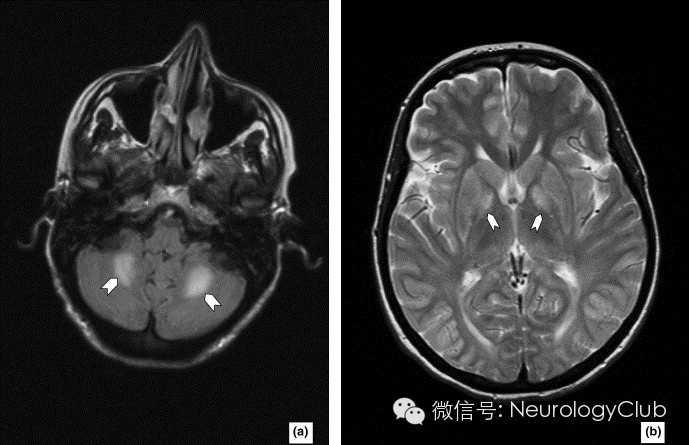

病例1

2岁患儿,女性。

(FLAIR:岛叶皮质及深部额叶脑回异常信号,邻近皮质下U形纤维)

(质子密度加权像[A]和FLAIR[B]提示双侧壳核和尾状核头线状高信号)